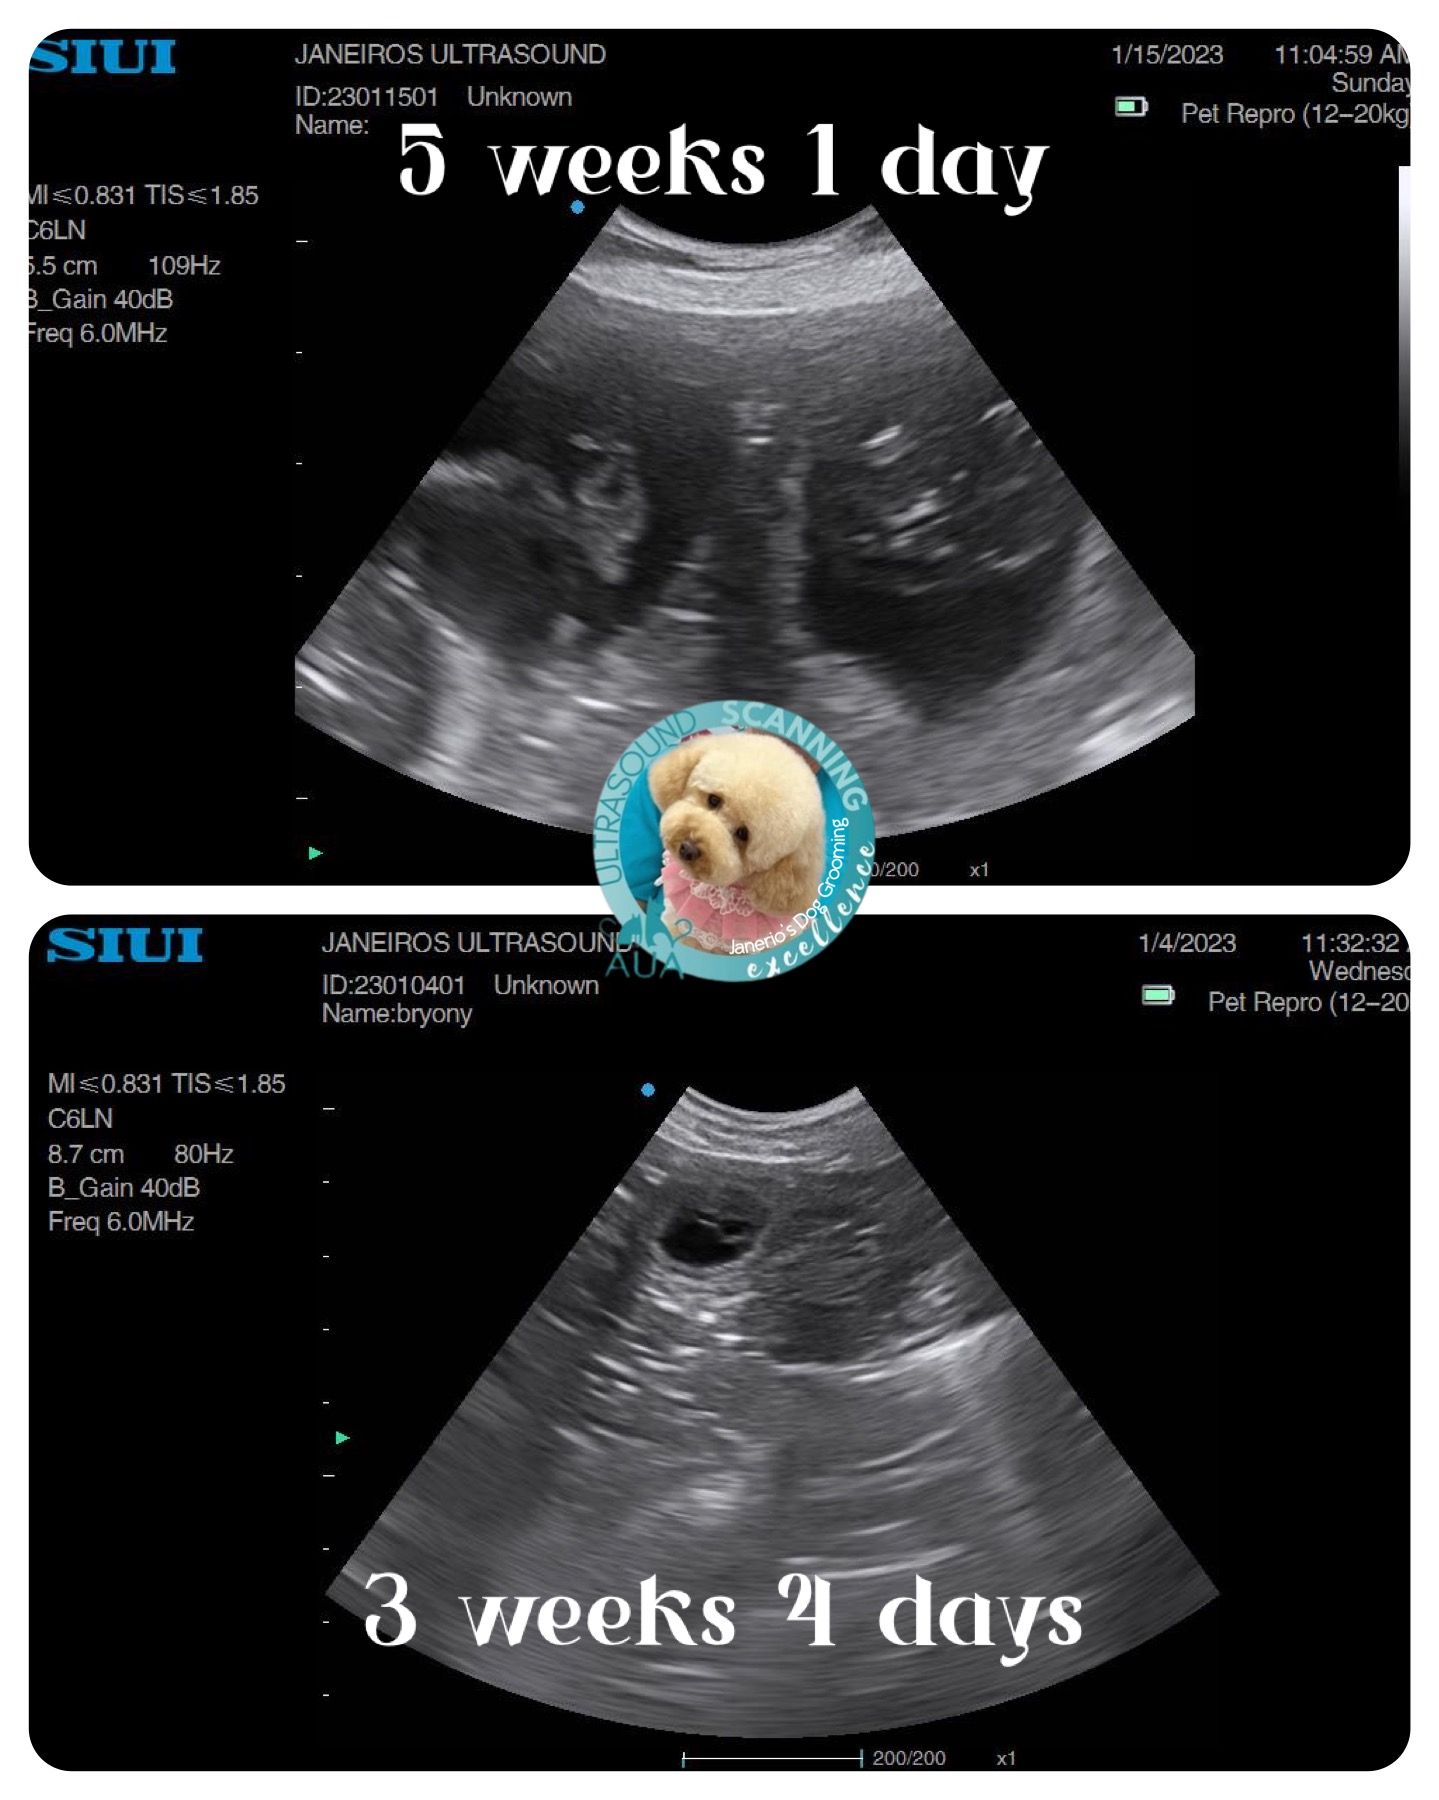

Nala came in for a scan just under 2wks ago. The sacs were tiny so we knew she had only just taken – much later than owner originally thought.

All I could do was confirm pregnancy at this stage and book her in for a rescan. We saw 3 sacks.

Spring forward to today. Measurements taken suggested 5wks and 1 day gestation and 6 sacs!!

The pictures and videos are so much clearer at this stage. Trust me.. don’t fib to you scanner regarding dates, it’s really not worth it! 😊